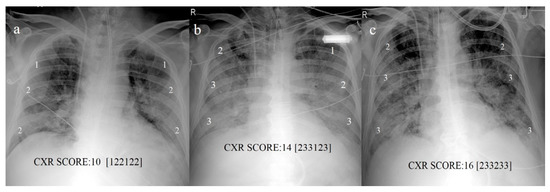

2.3. Chest X-ray: Scoring System

- Maroldi, R.; Rondi, P.; Agazzi, G.M.; Ravanelli, M.; Borghesi, A.; Farina, D. Which role for chest x-ray score in predicting the outcome in COVID-19 pneumonia? Eur. Radiol. 2020, 2, 1–7. [Google Scholar] [CrossRef]

- Toussie, D.; Voutsinas, N.; Finkelstein, M.; Cedillo, M.A.; Manna, S.; Maron, S.Z.; Jacobi, A.; Chung, M.; Bernheim, A.; Eber, C.; et al. Clinical and Chest Radiography Features Determine Patient Outcomes In Young and Middle Age Adults with COVID-19. Radiology 2020, 297, E197–E206. [Google Scholar] [CrossRef] [PubMed]

- Cozzi, D.; Albanesi, M.; Cavigli, E.; Moroni, C.; Bindi, A.; Luvarà, S.; Lucarini, S.; Busoni, S.; Mazzoni, L.N.; Miele, V. Chest X-ray in new Coronavirus Disease 2019 (COVID-19) infection: Findings and correlation with clinical outcome. La Radiol. Med. 2020, 125, 730–737. [Google Scholar] [CrossRef]